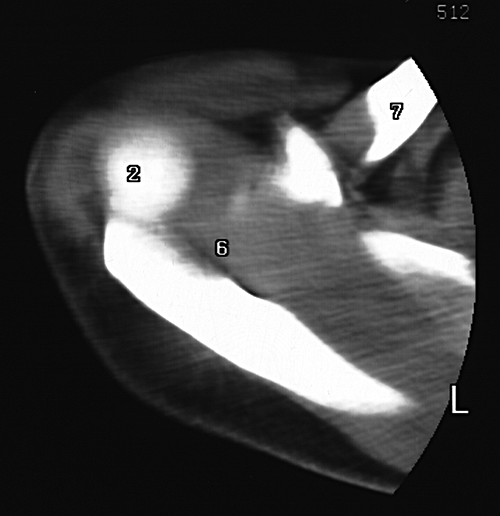

2. Head of humerus

6. Supraspinatus m.

7. Clavicle